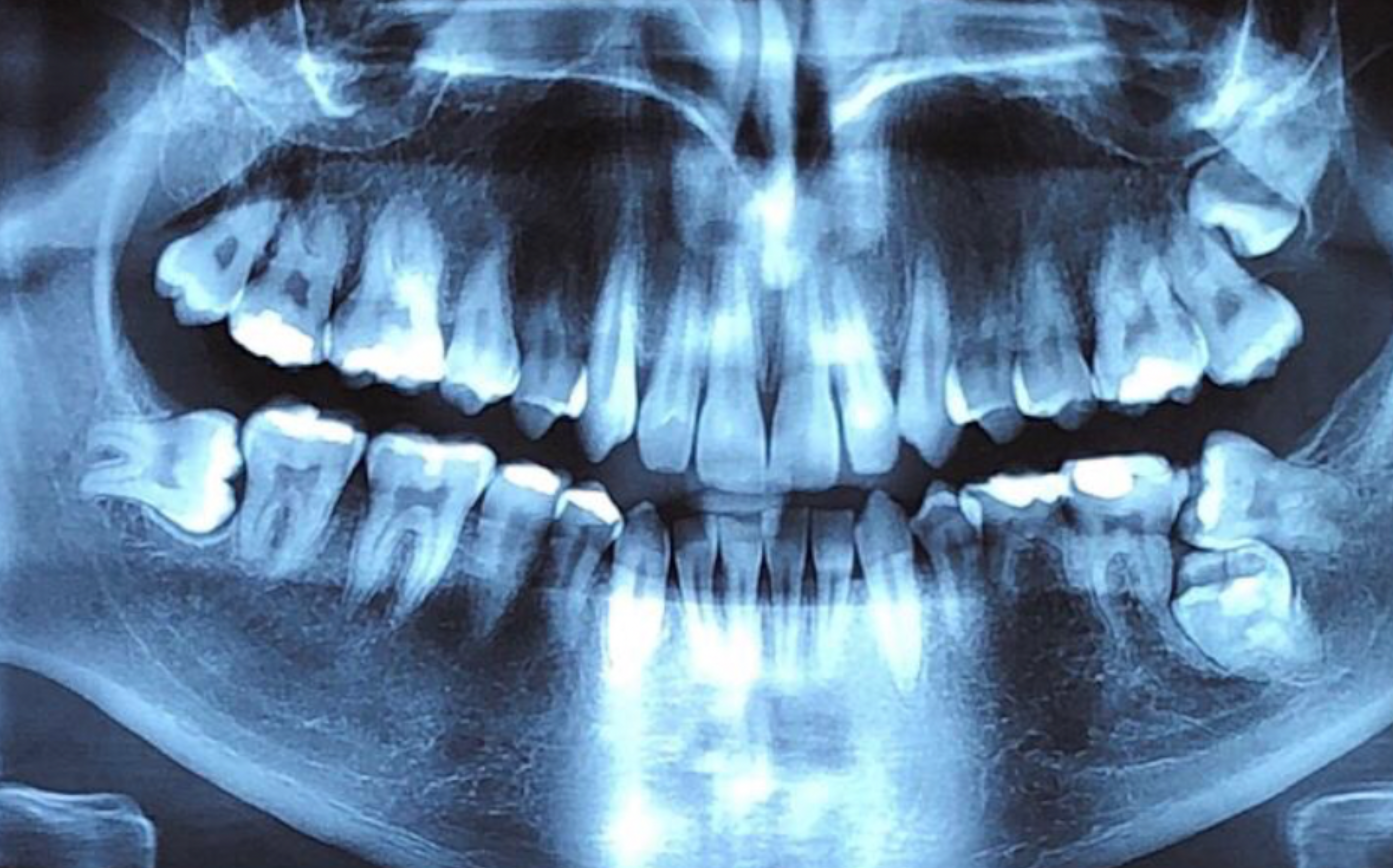

This webinar objectives are to Understand the importance of maintaining primary teeth, Know the complex anatomy of primary teeth,determine when to extract, learn new technologies and materials in pulpotomies and pulpectomies.

Video Length 17:39 min